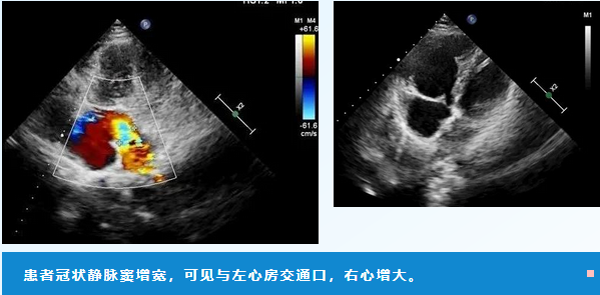

王女士再次赶到医院时天色已晚,寂静的诊室里,只能听到心脏跳动从机器中传来的音频。张若冰抽丝剥茧般追寻那束异常的血流,这一次终于明确了病因所在,确诊是“无顶冠状静脉窦综合征”。这是一种极罕见的先天性心脏病,冠状静脉窦位置隐蔽,确诊的难度可想而知。就这样,患者心中的“不足”终于被找到了!隐藏在心中的疑团茅塞顿开,王女士非常感动,连声感谢积水潭医院医生对待患者高度负责的精神,解开了自己多年的心结。张若冰将检查情况对王女士进行科普,并叮嘱她及时到心内科就诊。